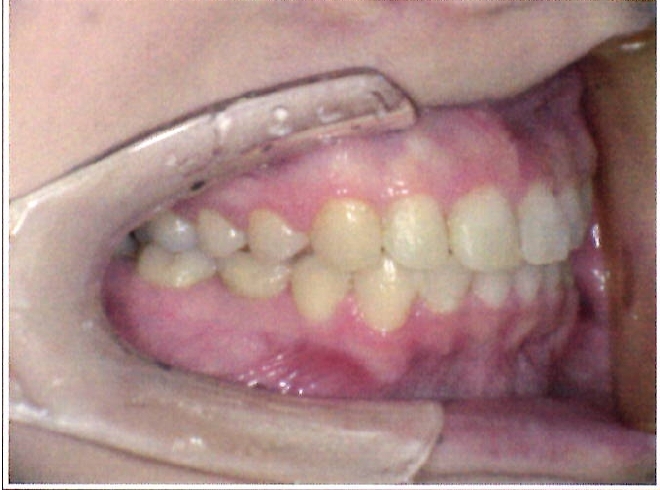

| 主訴・治療前の状態 | 過蓋咬合(噛み合わせが深く、下の前歯が見えない状態)により歯ぎしりができない状態でした。また、上下顎前歯部に叢生(クラウディング・ガタガタ)がありました。 |

| 治療内容 | 矯正治療により、過蓋咬合と上下の叢生を改善しました。 |

| 治療結果 | 適切な被蓋(上下の前歯の重なり)が得られ、下の前歯がきちんと見えるようになりました。上下の前歯の歯並びも美しく整い、しっかりと噛み合うようになりました。機能面・審美面ともに大きく改善した症例です。 |